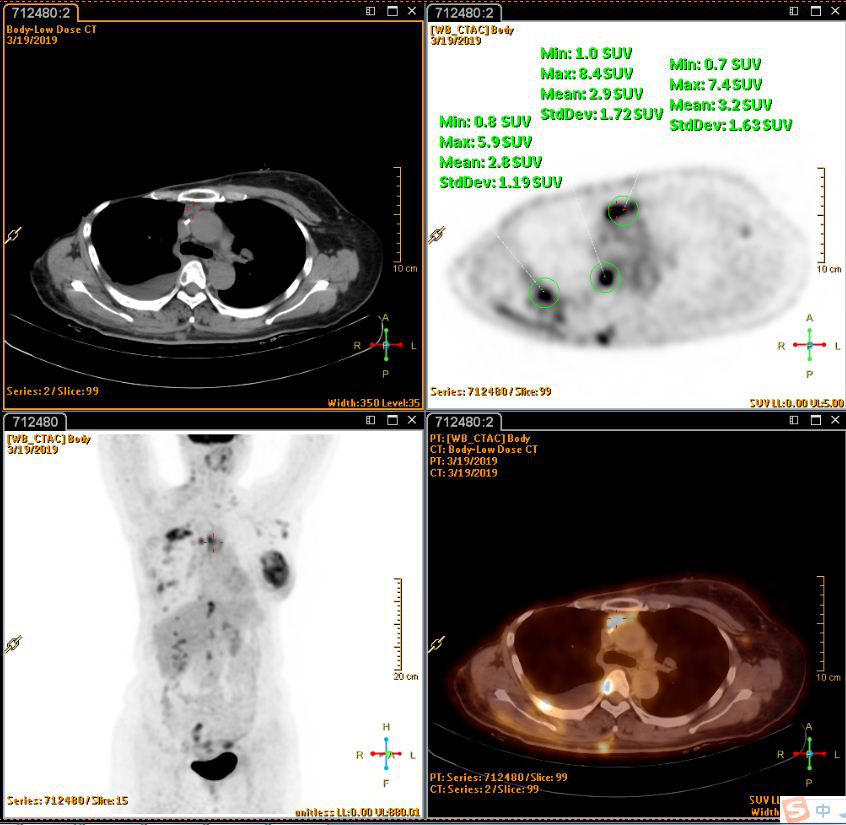

PET(2019-3-20):1.右乳癌术后改变,左侧乳腺腺体密实、左乳头周围皮肤增厚,葡萄糖代谢增高,考虑乳腺癌;颈部、纵隔、左侧腋窝、腹腔及腹膜后多发淋巴结转移,右侧胸膜转移,多发骨转移,多发肌肉转移;2.右侧液气胸,右肺炎症;肺下叶外基底段小结节,建议观察。

张3.png

图3